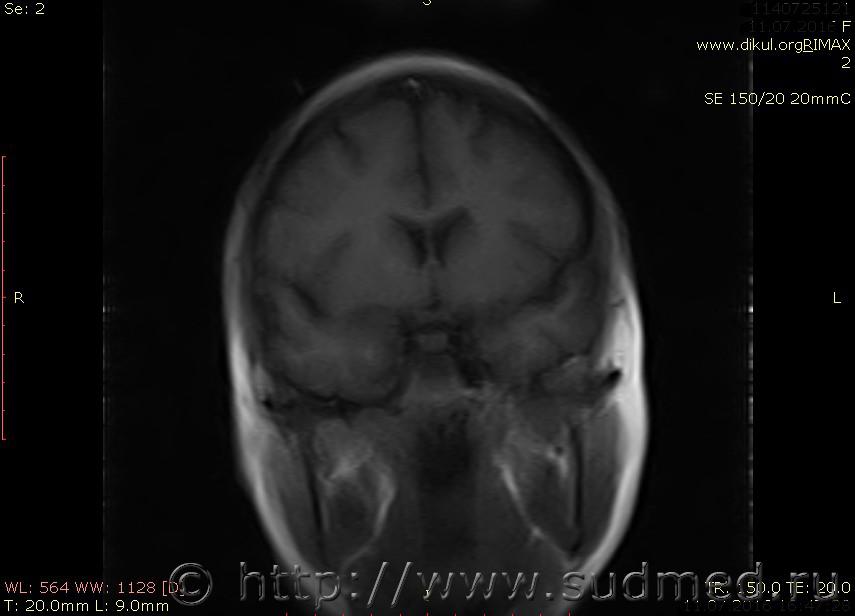

МРТ головного мозга показало: МР-данных за наличие очаговых изменений в веществе головного мозга на момент исследования не выявлено. МР-признаки нарушения соотношения в атланто-осевом суставе. Определяется ассиметрия положения зубовидного отростка С2 относительно боковых масс С1(справа 6,5; слева 4 мм.)

МР-признаки нарушения соотношения в атланто-осевом суставе. Определяется ассиметрия положения зубовидного отростка С2 относительно боковых масс С1(справа 6,5; слева 4 мм.)

Сама по себе эта информация даёт основания подозревать вывих первого шейного позвонка, но однозначно не свидетельствует о наличии вывиха. Нужно смотреть на снимках наличие реакции со стороны мягких тканей, в т.ч. связочного аппарата, нужно анализировать особенности неврологической патологии, её динамику и проч.

Посмотрите пожалуйста снимки, надеюсь на них видны позвонки С1,С2?

Прошу прощения, попробую снова прикрепить файлы. Данные учреждения и пациента убраны.